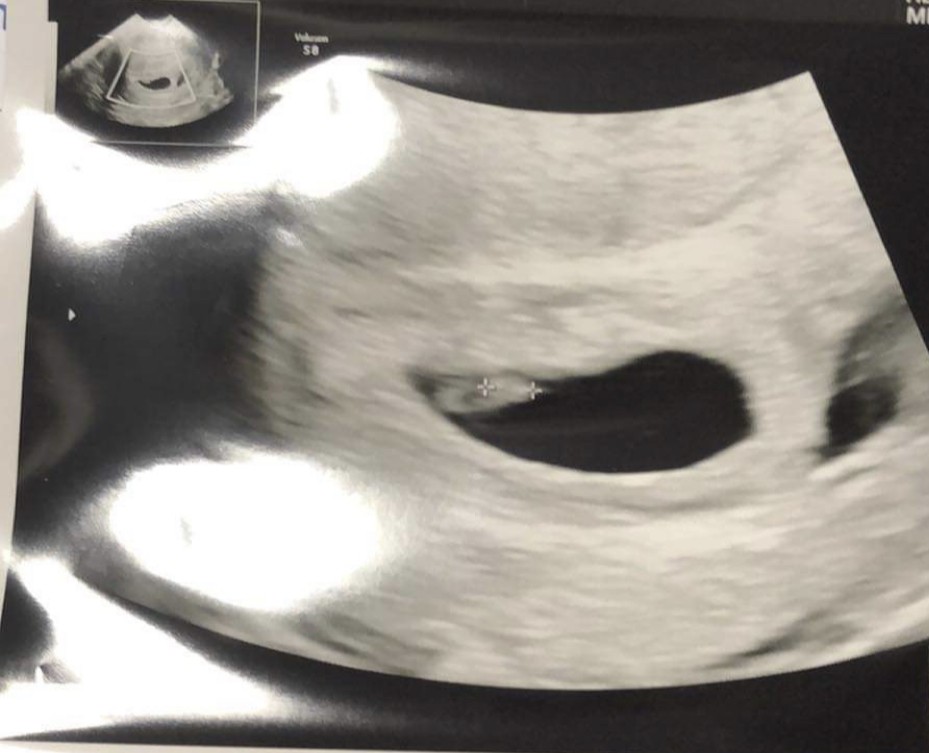

Dziewczyny miałam mieć wizytę w środę ale lekarz ma pilny wyjazd i przyjął mnie dzisiaj.

Z OM 6+5 ale z USG 5+6 tc wiec ciąża trochę młodsza.

Najważniejsze ze maluszek jest już widoczny i serduszko tez już bije ❤️

• B7A394EF-56C5-48BD-B2C3-649EB328CCE0.jpeg

B7A394EF-56C5-48BD-B2C3-649EB328CCE0.jpeg

84,8 KB · Wyświetleń: 104